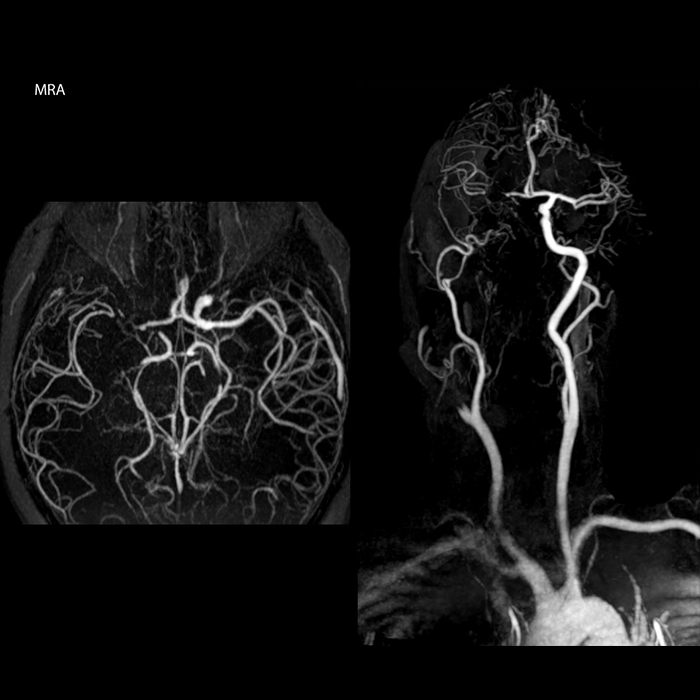

When multiple sclerosis (MS) is suspected, clinicians need a diagnosis early on, so treatment can begin as soon as possible. “A challenge for imaging is that MS lesions in the brain and spine may be very small,” says Dr. Savatovsky. “We need precise imaging to tell exactly where the lesion is, so we need high quality, very high resolution images, preferably in 3D[1]. We need to know if a high T2 signal intensity is suggestive of MS or just aspecific. And we want to visualize active lesions very well.”

“Ingenia 3.0T provides us very good image quality with high SNR, even if we push the resolution. For example, in FLAIR images we may have an isotropic resolution of 0.9 mm. Ingenia allows us to use 3D T1 TSE with BrainView, which has a better sensitivity than 2D spin echo imaging[2] and 3D gradient echo imaging. Ingenia also provides highly reproducible exams, which is important in MS imaging so that follow-up exams at different time points are done the same way.”

For MS imaging in the brain, Dr. Savatovsky uses 3D FLAIR as the basic sequence to visualize the lesions and assess the situation and lesion load. “We count the lesions in each location to determine if the criteria of the disease are fulfilled. We use a T2-weighted sequence because our neurologists are used to it. We compare the lesion load on FLAIR with a 3D T1 post-contrast sequence to help us determine whether lesions are old or new. We typically administer the contrast before the patient enters the machine because it shortens the examination time and allows to visualize active lesions that tend to be more visible after several minutes. When a differential diagnosis is difficult, we add sequences such as susceptibility imaging, because some focal MS lesions have a small vein in the center[3].”